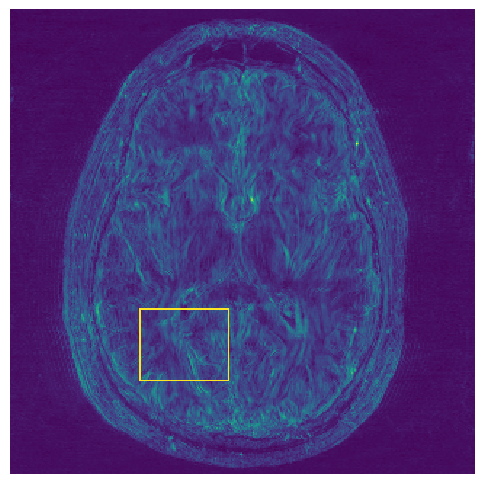

Figure 3: Reconstructions results. Rows 1 and 3: Examples of comparing the ground truth (GT) fully sampled image to the reconstructed images obtained by the three models (1-3), NPB-REC, baseline, E2E-VarNet trained with Dropout, and the NPB-REC std. map at accelerations R=4𝑅4R=4italic_R = 4, R=8𝑅8R=8italic_R = 8, respectively. Rows 2 and 4: The corresponding annotated ROIS of Nonspecific white matter lesions.

Fig. 3 presents examples of reconstruction results obtained by (1) our NPB-REC approach, (2) the baseline, and (3) Monte Carlo Dropout, for equispaced masks with two different acceleration rates R=4𝑅4R=4italic_R = 4 and R=8𝑅8R=8italic_R = 8. The reconstructed images predicted by the three models are smoother than the reference image. This is due to the fact that all the models were trained with SSIM loss, which tends to produce overly smooth reconstructions while preserving the diagnostic content and the anatomical features Sriram et al. (2020a). These images can be enhanced by dithering the image by adding a small amount of random Gaussian noise to produce a more textured reconstruction, as proposed in Sriram et al. (2020b).

Table 1 presents the mean PSNR and SSIM metrics, calculated over the whole inference set, for the three models. Our NPB-REC approach achieved significant improvements over the other methods in terms of PSNR and SSIM (Wilcoxon signed-rank test, pmuch-less-than\ll1e-4, except for SSIM values in line W, R=4𝑅4R=4italic_R = 4 where they are roughly the same for NPB-REC and Baseline). The improvement in the reconstruction performance can be noted both quantitatively from the metrics, especially for masks with acceleration rate R=8𝑅8R=8italic_R = 8, and qualitatively via the images of annotations, where our results show less smoothness than those obtained by Dropout.